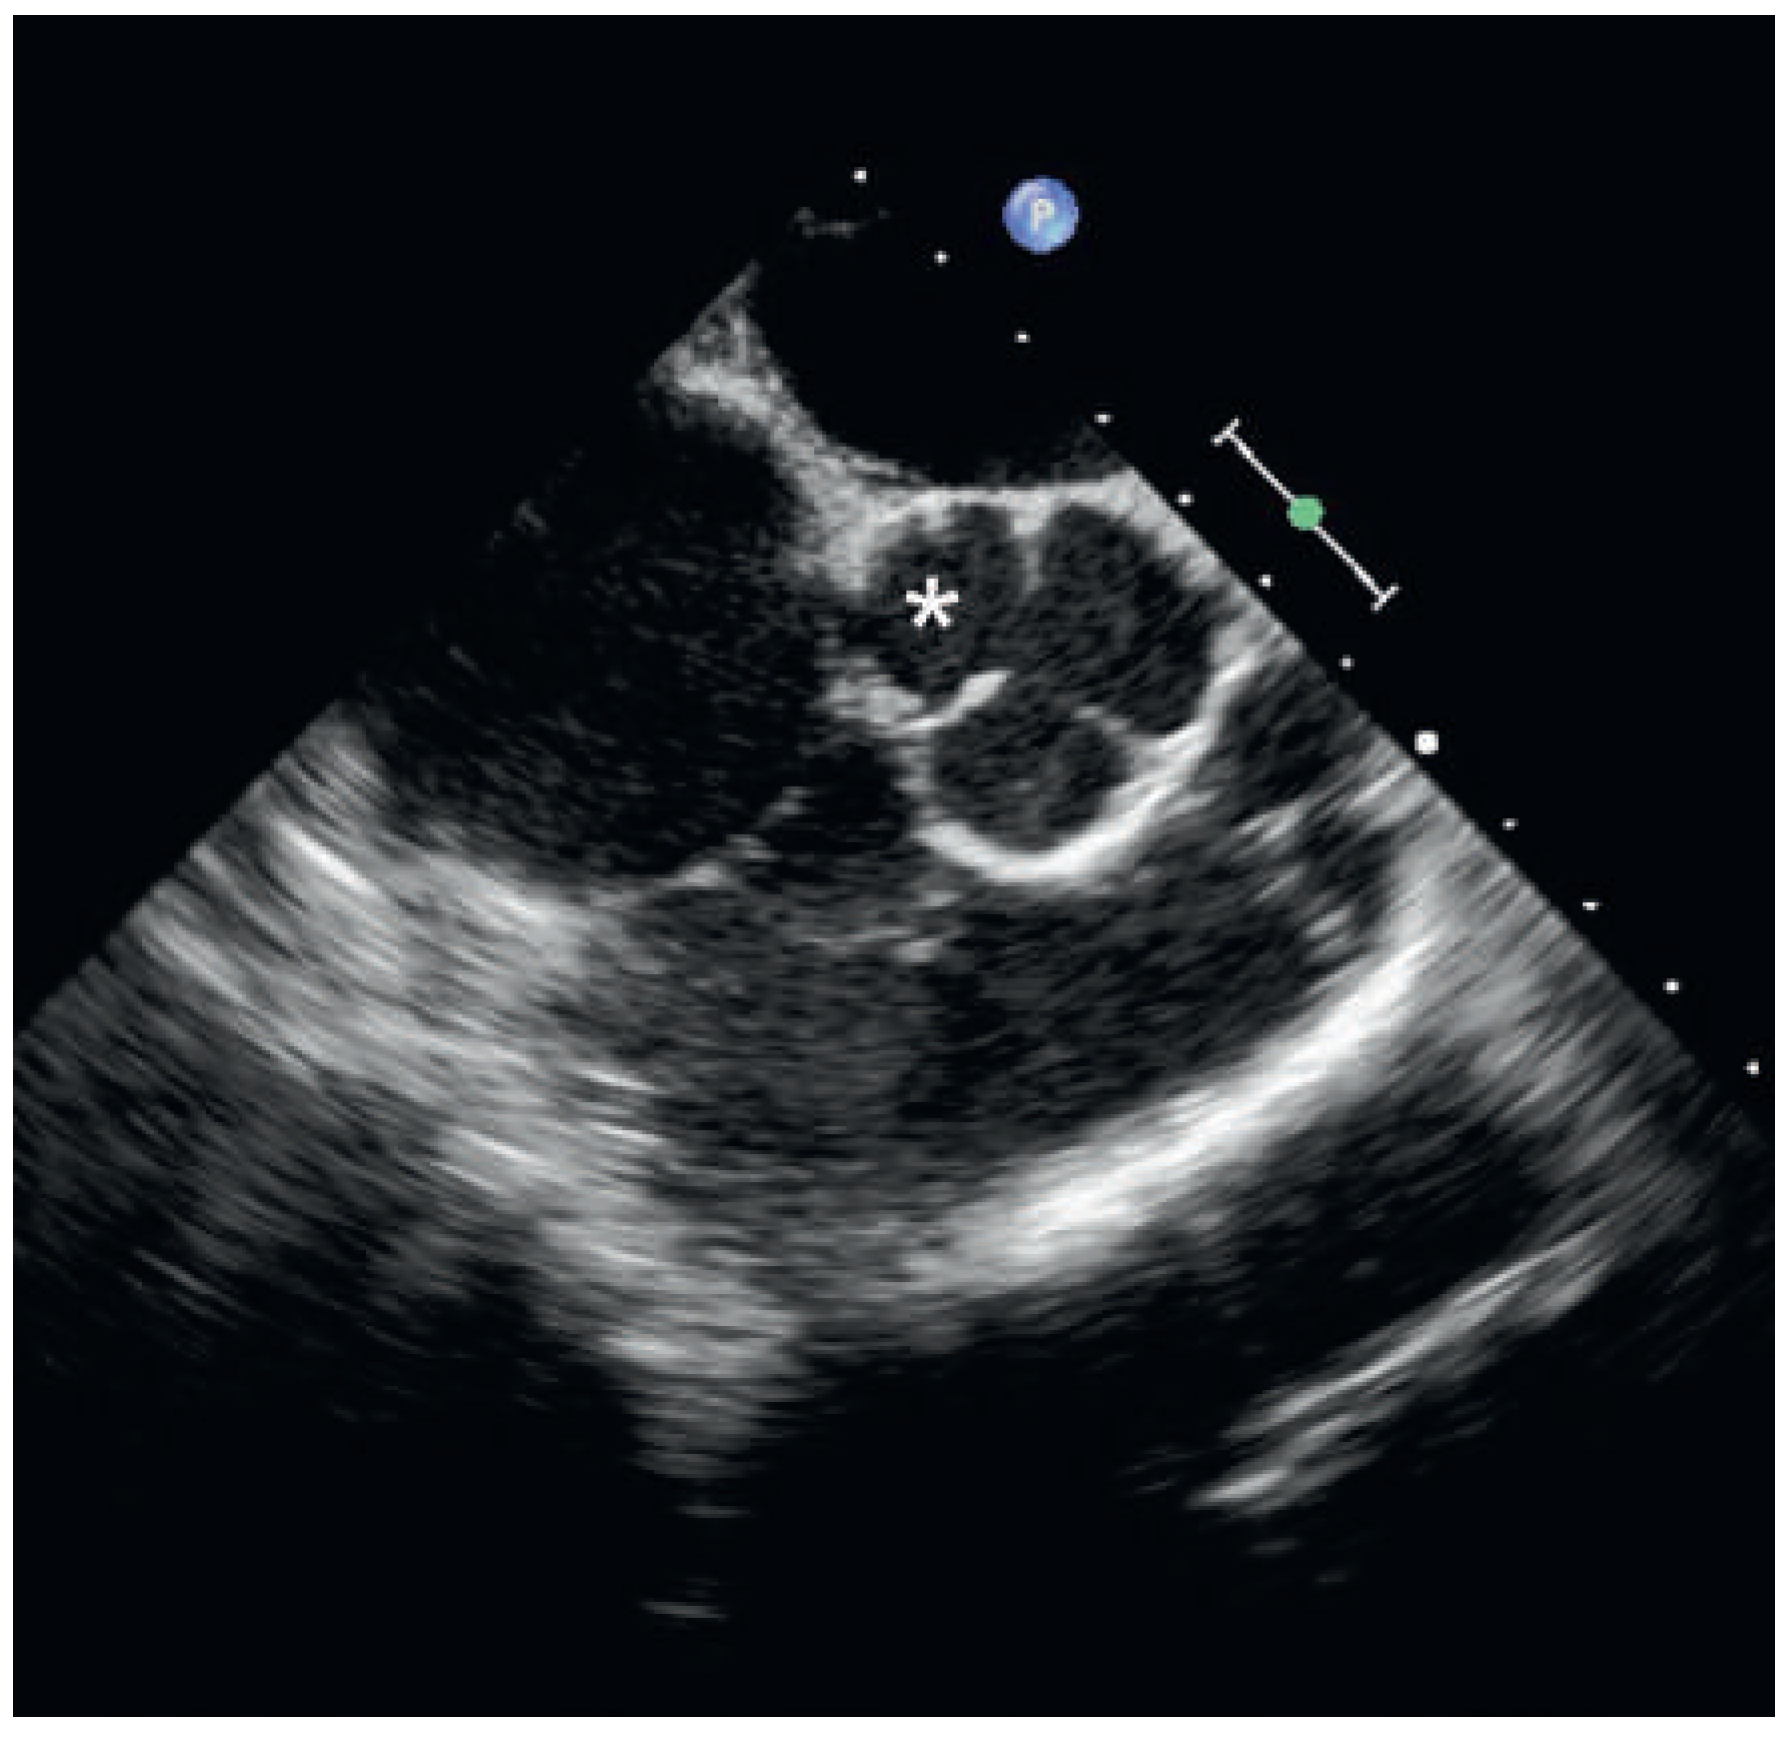

Case report